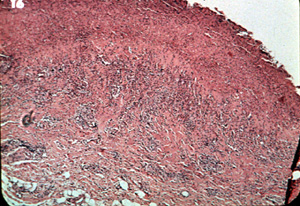

Inflamación

La intensa inflamación crónica en el tejido conjuntivo

también tiene una tendencia a bloquear la reflexión de la luz

roja. Esta micrfotografía ilustra como la inflamación crónica

puede evitar también la reflexión de la luz. Tiene el efecto de

espesar el área entre la superficie y los vasos sanguíneos

subyacentes. |